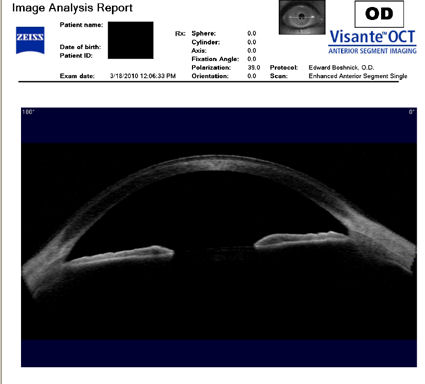

Следующие изображения были получены с использованием метода, называемого оптической когерентной томографией, или ОКТ. Прибор позволяет получить изображение в поперечном сечении путем сканирования передней части глаза (переднего сегмента) лучом света. Думайте об этом как об ультразвуке, использующем свет вместо звуковых волн для создания изображения живых тканей.

На снимке ниже показана роговица пациента, у которого после операции LASIK развилась эктазия. Пациент носит жесткие склеральные контактные линзы. Вы можете видеть выпячивание роговицы в самом слабом месте (эктазия), что приводит к сильному искажению зрения. Очки и мягкие контактные линзы неэффективны для таких глаз, как этот. Нажмите на изображение, чтобы увеличить.

На следующих двух снимках ниже показана жесткая склеральная контактная линза на роговице после операции LASIK.

Изображения любезно предоставлены доктором Эдвардом Бошником, который посвятил свою практику восстановлению качественного зрения и информации о эктазия после операции LASIK .